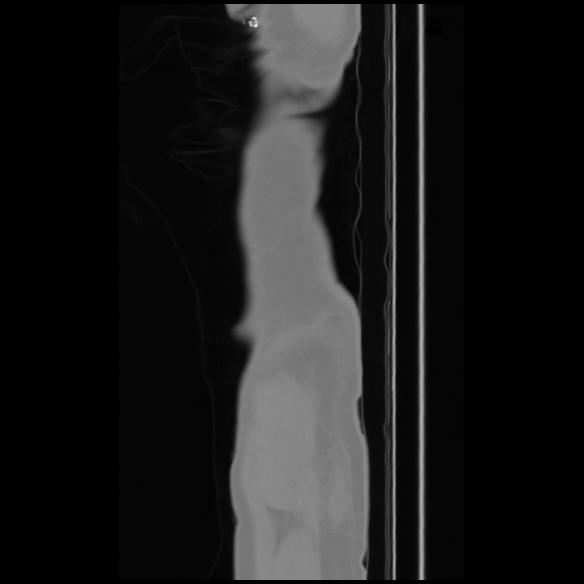

7 CUERPO,CE,Sagittal,3.000,CUERPO,Sagittal,